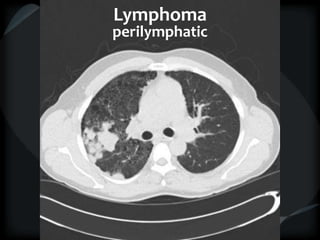

LYMPHOHEMATOGENOUS

PERYLYMPHATIC RANDOM

axial skeleton end of vessels

upper lobes basilar

-lymphoma -vasculitis

-Kaposi's -amyloidosis

Lymphoma

perilymphatic